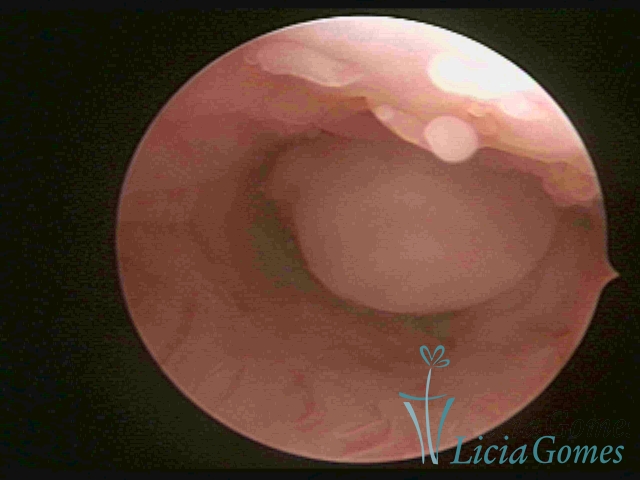

ENDOCERVICAL POLYPS

Benign tumors resulting from the reactive focal proliferation to inflammatory processes or hyperestrogenism situations, which may be sessile (with a large implantation) or stalked.